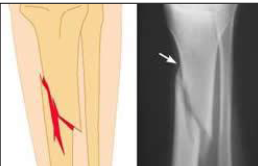

What type of fracture is this?

Spiral fracture

more common in younger age